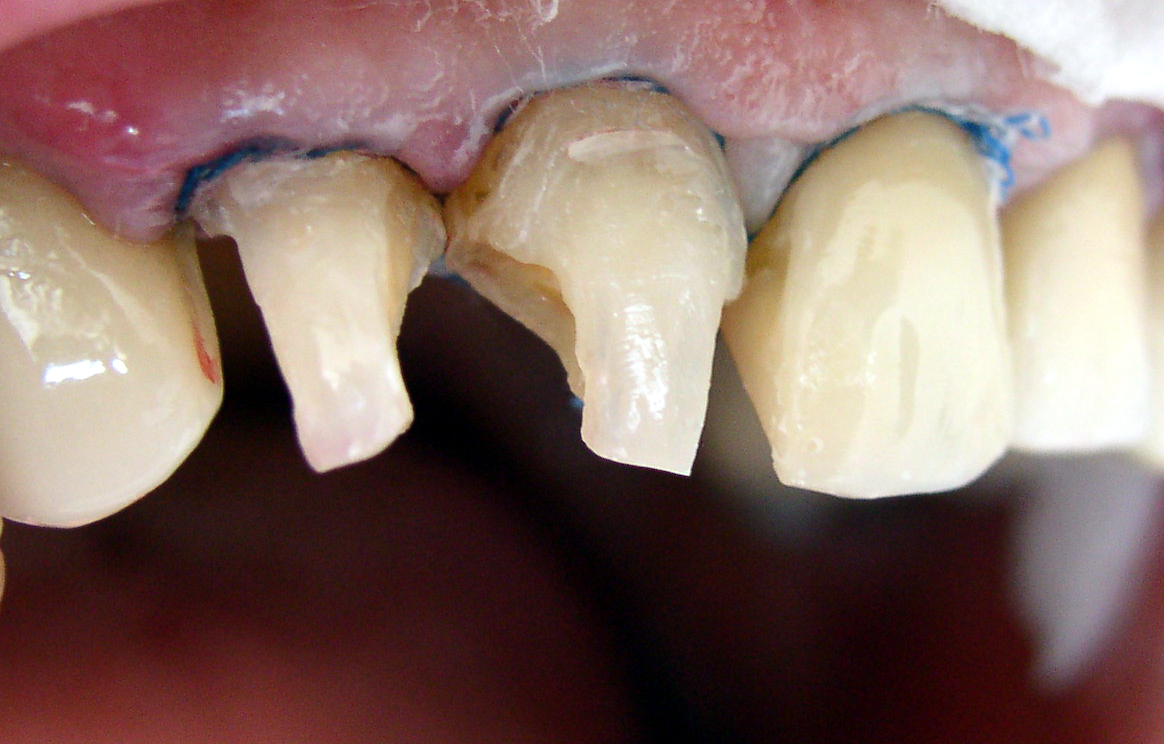

Pacjentka zgłosiła się z powodu dyskomfortu i okresowego krwawienia z dziąseł. Po uwolnieniu zębów ze starych wypełnień usunięto tkanki zmienione próchnicowo. Zęby odbudowano materiałem złożonym i starannie zweryfikowano pobrzeże wypełnień. Zastosowany materiał Filtek Supreme pozwolił na uzyskanie zgodności kolorystycznej z uzupełnieniami stałymi na zębach jednoimiennych po stronie lewej.